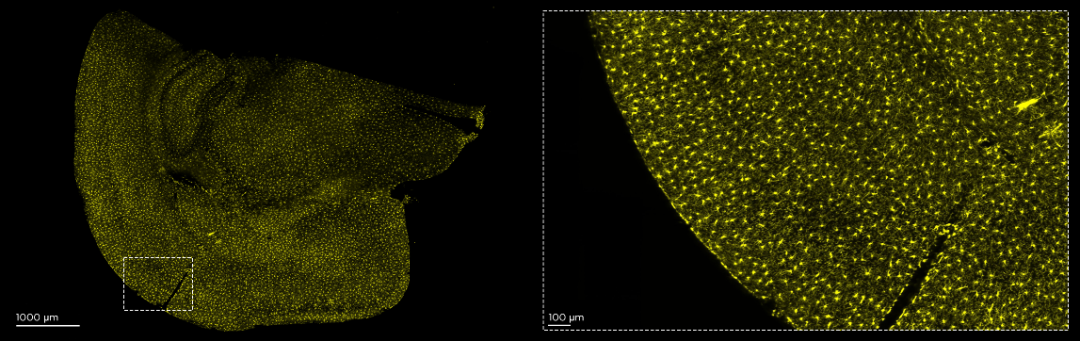

2024年8月5日,上海交通大学熊丽琴老师在《ACS Nano》杂志上发表了题为“Fluorescent pdots facilitate high-resolution mapping of the Intact meningeal vascular network and eye−brain connections”的学术文章,我司创始人李小卫博士为合作作者。在该项工作中,研究团队开发了一种实用的实验方法,以确保完整的脑膜在形态上展开并固定在琼脂糖凝胶中。在高亮度聚合物点 (Pdots) 作为探针的帮助下,可以对完整背侧脑膜上的血管网络进行宏观和详细的成像。脑膜血管沿矢状窦上部对称分布,脑膜血管的分布具有一定程度的层次结构。脑膜是从外到内的较厚的血管和毛细血管网络。此外,毛细管的直径为 3.96 ± 0.89 μm。有趣的是,小鼠中枢神经系统中的脑膜原血管的直径为 4.18 ± 1.18 μm,这在以前没有报道过。值得一提的是,研究团队发现脑肿瘤的原位异种移植物引起了角膜新生血管的出现和视神经微血管的形态学变化。综上所述,该项工作为脑膜血管相关疾病的后续研究提供了一种有效的基于 Pdots 的成像方法,并说明了眼睛可以作为预防和诊断脑部疾病的窗口。

在该研究中,使用了厚组织3D成像光片显微镜—MegaSPIM,对高亮度聚合物点 (Pdots)灌注治疗后的完整背侧脑膜血管进行光片显微成像,这是MegaSPIM首次在国内科学研究中得到应用。目前MegaSPIM已经由Chung教授创办的公司Lifecanvas Technoloiges(LCT)商业化,并面向全球销售。诒福科技和千欣仪器为中国用户提供这两款产品及其他LCT产品的销售和技术支持。

100μm 厚的小鼠大脑未透明化切片成像:Iba-1(黄色),用 Megatome 切片并用 MegaSPIM 以 15X 成像